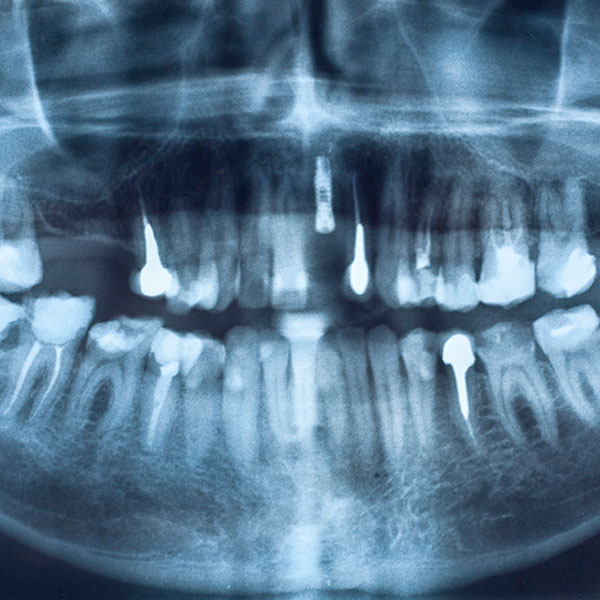

Такое исследование позволяет определить проблемы не только 2−3 соседних зубов, но и диагностировать состояние всей зубочелюстной системы и прилегающих структур, выявить на ранней стадии кисты, гранулемы, опухоли. Благодаря возможностям панорамного снимка удается более четко определить пораженный зуб, обнаружить различные аномалии развития, уточнить оптимальное место для вживления импланта, максимально качественным образом провести ортодонтическое и пародонтологическое лечение.

Несмотря на то, что прицельный снимок зубов по-прежнему широко используется в стоматологии, все более значимую роль играют и другие виды диагностики. Чтобы добиться максимально качественного результата лечения зубов, специалисты клиники Совершенная улыбка активно обращаются к ортопантомограмме

Панорамный снимок становится все более востребованным в качестве скрининговой методики. Высокая скорость проведения исследования, использование современного оборудования позволяют считать такой вид диагностики абсолютно безопасным. Она может проводиться по мере необходимости, несколько раз в году.